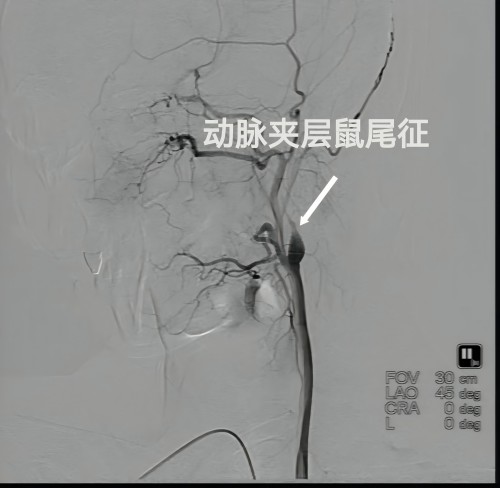

经张瑶副主任医师接诊后详细询问,患者并无过往病史。然而,头部核磁共振检查结果显示患者左侧颈内动脉闭塞,通过进一步的全脑血管造影检查,确诊为左侧颈内动脉夹层所致的左侧颈内动脉重度狭窄。在经过积极的抗血小板聚集治疗后,李女士的头痛症状已得到有效缓解,并于今日康复出院。为确保疗效,医生建议李女士按照医嘱,规律进行抗血小板聚集治疗,并于6个月后复查,以评估血管狭窄的改善情况。

张瑶副主任医师详尽阐述了头颈部动脉夹层的发病机理:该病主要由于颈部或颅内动脉内膜损伤并发生撕脱,导致血液渗入血管壁内部,形成壁内血肿,进而引发血管壁各层分离。这一过程可能导致血管狭窄、闭塞或形成夹层动脉瘤。发病的危险因素主要包括外伤、高血压、遗传因素及动脉粥样硬化等。相关统计数据显示,头颈部动脉夹层约60%的病例发病原因不明,而剩余40%的病例则与打喷嚏、剧烈咳嗽、颈部按摩、体育活动等有关。

治疗策略主要依赖于药物治疗,包括抗血小板药物及抗凝药物。对于那些对药物治疗反应不佳的头颈部动脉夹层患者,可能需要通过血管内介入手术来进行血管修复。